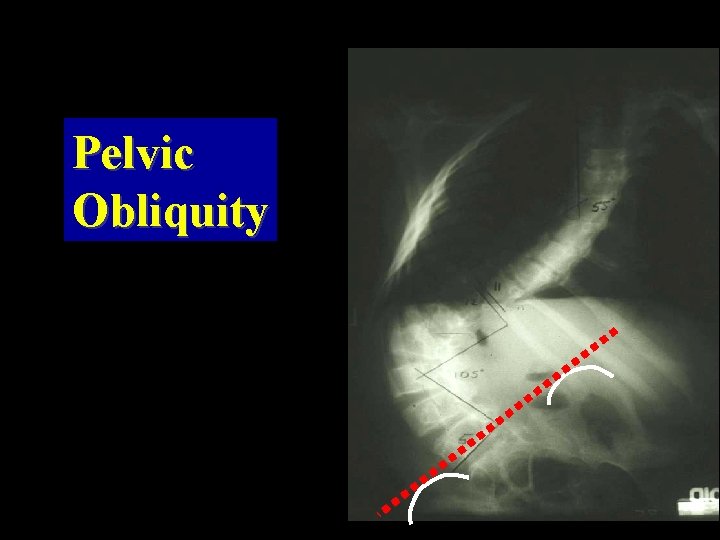

Pelvic Obliquity